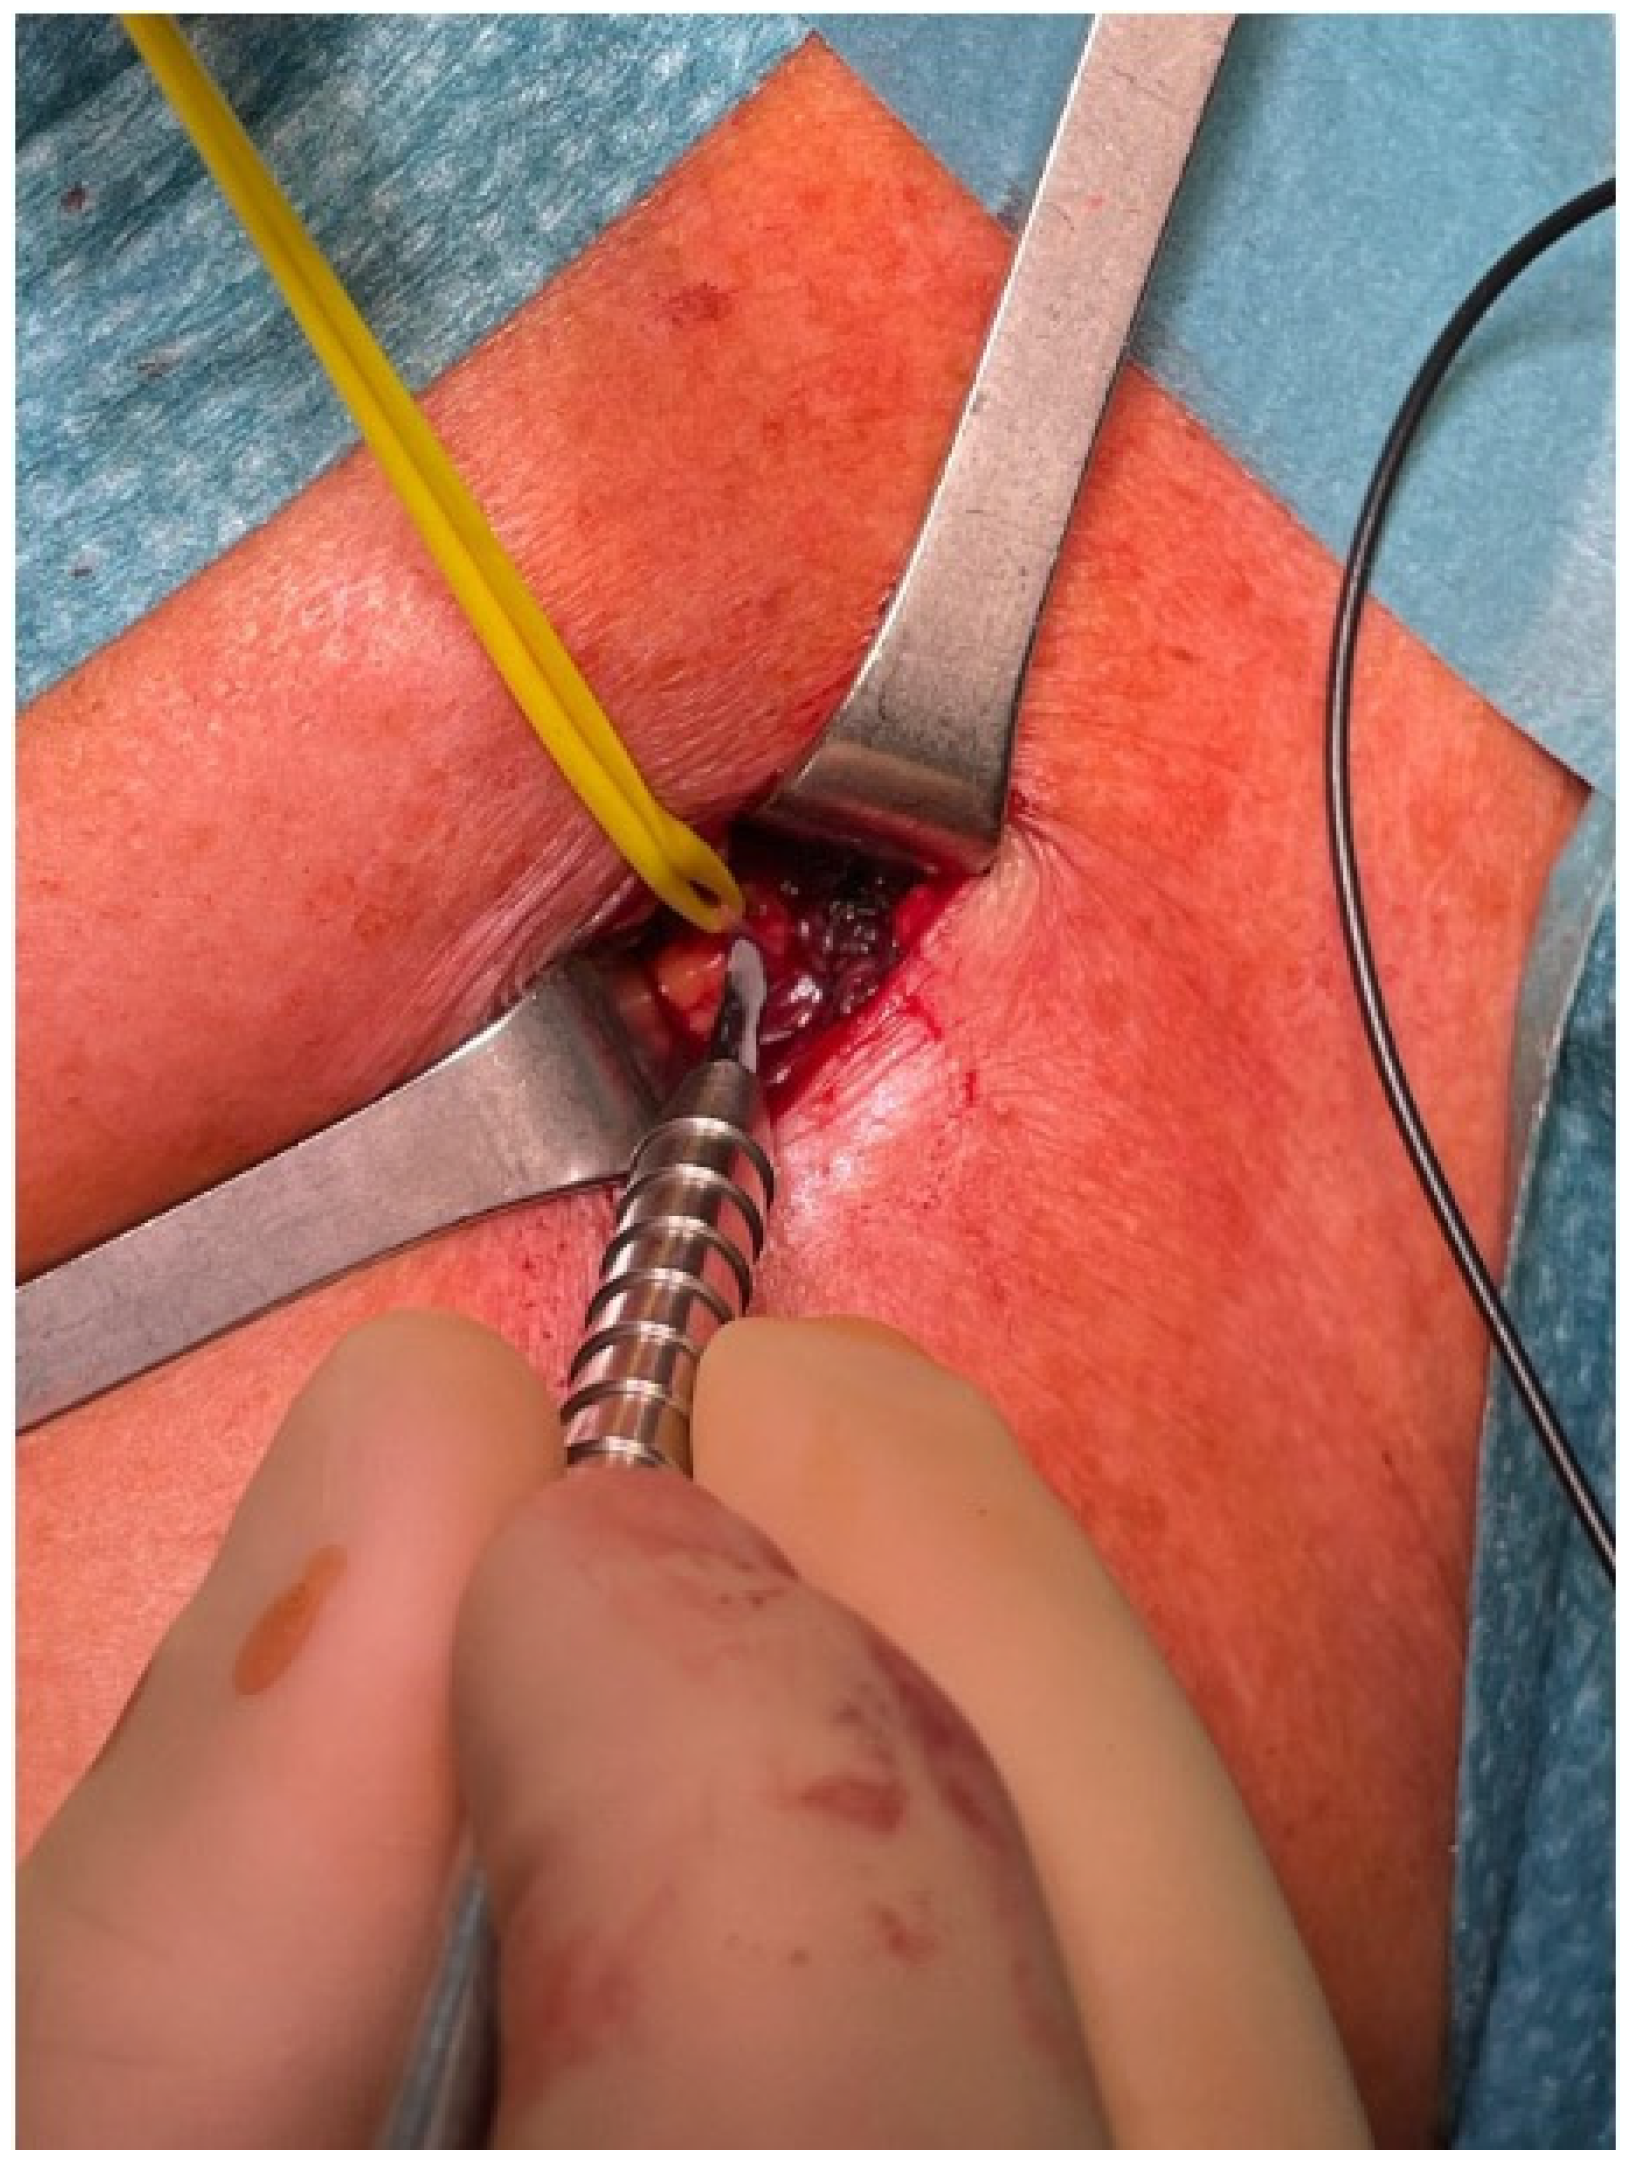

3.5. Selective Peripheral Neurectomy